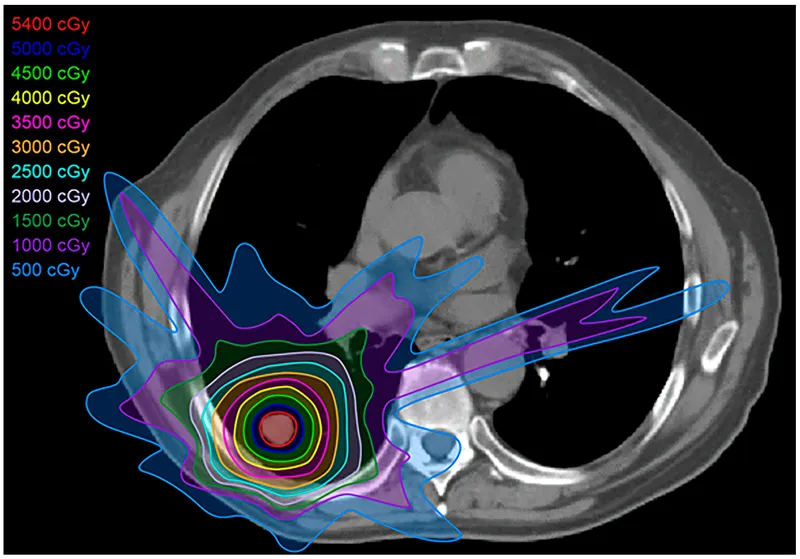

- Delivers radiation by modulating (varying) intensity of multiple small radiation beams.

- Primary Aim: Achieve highly conformal dose distributions to target volumes while sparing surrounding healthy tissues.

⭐ IMRT enables creation of concave dose distributions, crucial for complex tumor shapes near critical organs, unlike conventional 3D-CRT (3D Conformal Radiation Therapy).

- Integral Dose: Larger volume of normal tissue receives low radiation dose ("low-dose bath").

⭐ Despite superior OAR sparing, IMRT results in a larger low-dose bath to normal tissues, posing a theoretical ↑ risk of secondary cancers in long-term survivors.

⭐ IMRT uses Multi-Leaf Collimators (MLCs) that move dynamically during treatment to shape the radiation beam and modulate its intensity, allowing for highly conformal dose distributions to complex tumor shapes while sparing surrounding normal tissues. This process is often referred to as "painting" the dose onto the tumor volume slice by slice or arc by arc (for VMAT).

⭐ IMRT facilitates "dose painting": delivering heterogeneous doses within the target volume, escalating dose to high-risk subvolumes while concurrently sparing adjacent critical structures more effectively than 3D-CRT. This is particularly useful for boosting resistant tumor areas.